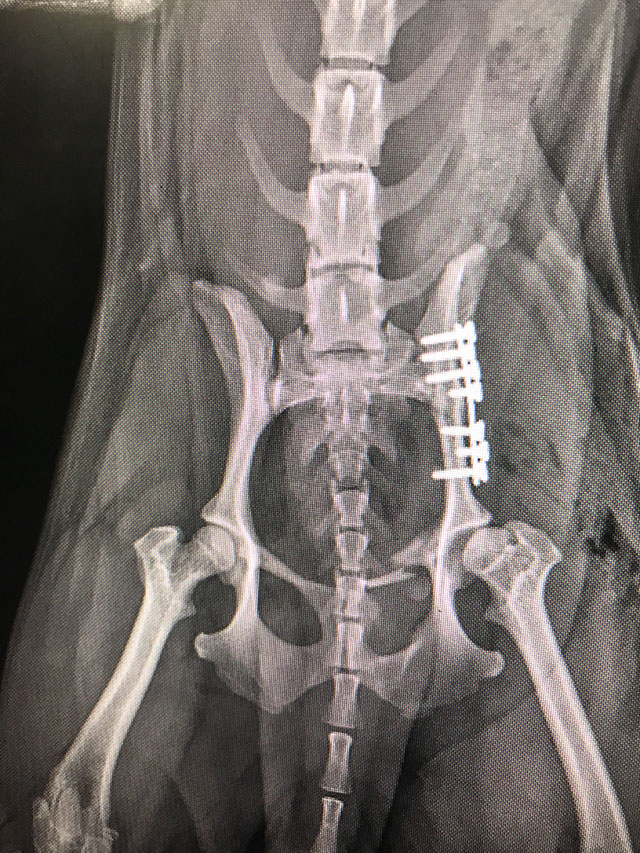

Osteosynteza

• Osteosynteza

Jest to zabieg polegający na stabilizacji złamania kości za pomocą implantów.